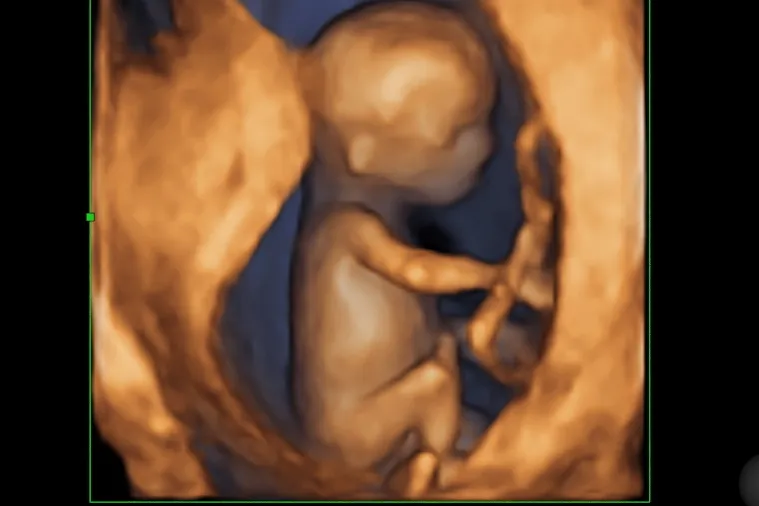

Pierwszą okazją do próby oceny płci jest zazwyczaj badanie USG genetyczne, wykonywane między 11. a 14. tygodniem ciąży. W tym okresie doświadczony lekarz, dysponujący certyfikowanym sprzętem, może podjąć próbę oceny płci na podstawie tzw. "kąta płciowego" guzka płciowego. Guzek ten jest prekursorem zarówno prącia, jak i łechtaczki. Jeśli jego nachylenie względem kręgosłupa jest większe niż 30 stopni, z dużą dozą prawdopodobieństwa można mówić o chłopcu; mniejszy kąt sugeruje dziewczynkę. Muszę jednak podkreślić, że skuteczność tej metody waha się w granicach 75-95% i jest obarczona sporym ryzykiem błędu. Wiele zależy od ułożenia dziecka, jakości obrazu i, co najważniejsze, doświadczenia osoby wykonującej badanie. Dlatego też, jeśli poznanie płci jest dla Państwa priorytetem, warto podchodzić do tej wczesnej oceny z pewną dozą ostrożności.

Jeśli chodzi o ultrasonograficzną ocenę płci, USG połówkowe, wykonywane między 18. a 22. tygodniem ciąży, to absolutny "złoty standard". W tym okresie narządy płciowe są już na tyle rozwinięte i wyraźne, że ich identyfikacja jest znacznie łatwiejsza i pewniejsza. Skuteczność oceny płci w tym czasie wynosi ponad 98-99%, co czyni ją najbardziej wiarygodną metodą wizualną. Aby jednak ocena była trafna, muszą być spełnione pewne warunki:

Z mojego doświadczenia wynika, że to właśnie na tym badaniu większość rodziców z radością dowiaduje się, czy spodziewają się chłopca, czy dziewczynki.